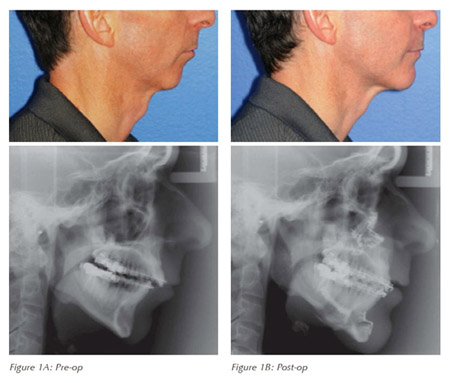

In patients having difficulty with other treatments, surgical procedures for the nose and throat can be a beneficial alternative. Skeletal surgical procedure which involves repositioning the lower and/or upper jaws in a forward manner also proves to be very effective. Surgical therapy can also be effective when used as an adjunct to improve tolerance and success with CPAP or an oral appliance.

YES, once all the lifestyle factors are corrected and jaw and tongue position corrected with Orthognathic surgery, in most cases patient’s dependence on oral appliance and CPAP machine is avoided.

What is exactly done in surgical procedure?

You can refer to Orthognathic surgery section in our braces treatment page for more details. click here to know more